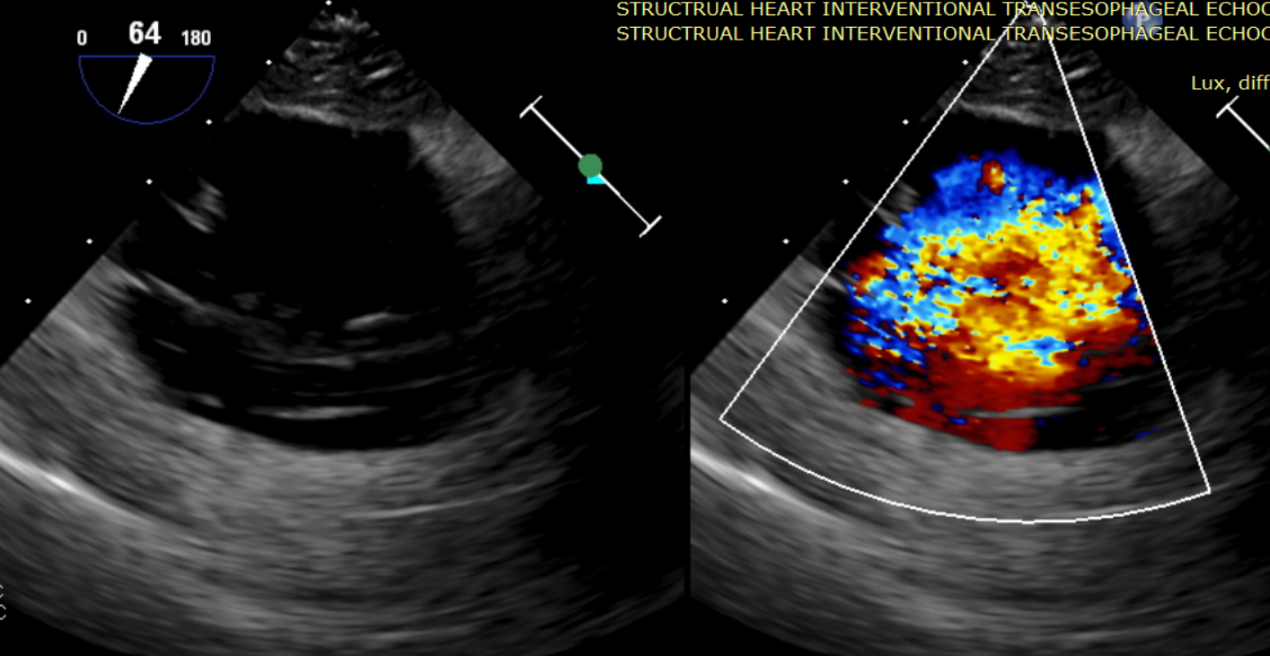

術前超聲提示大量三尖瓣反流